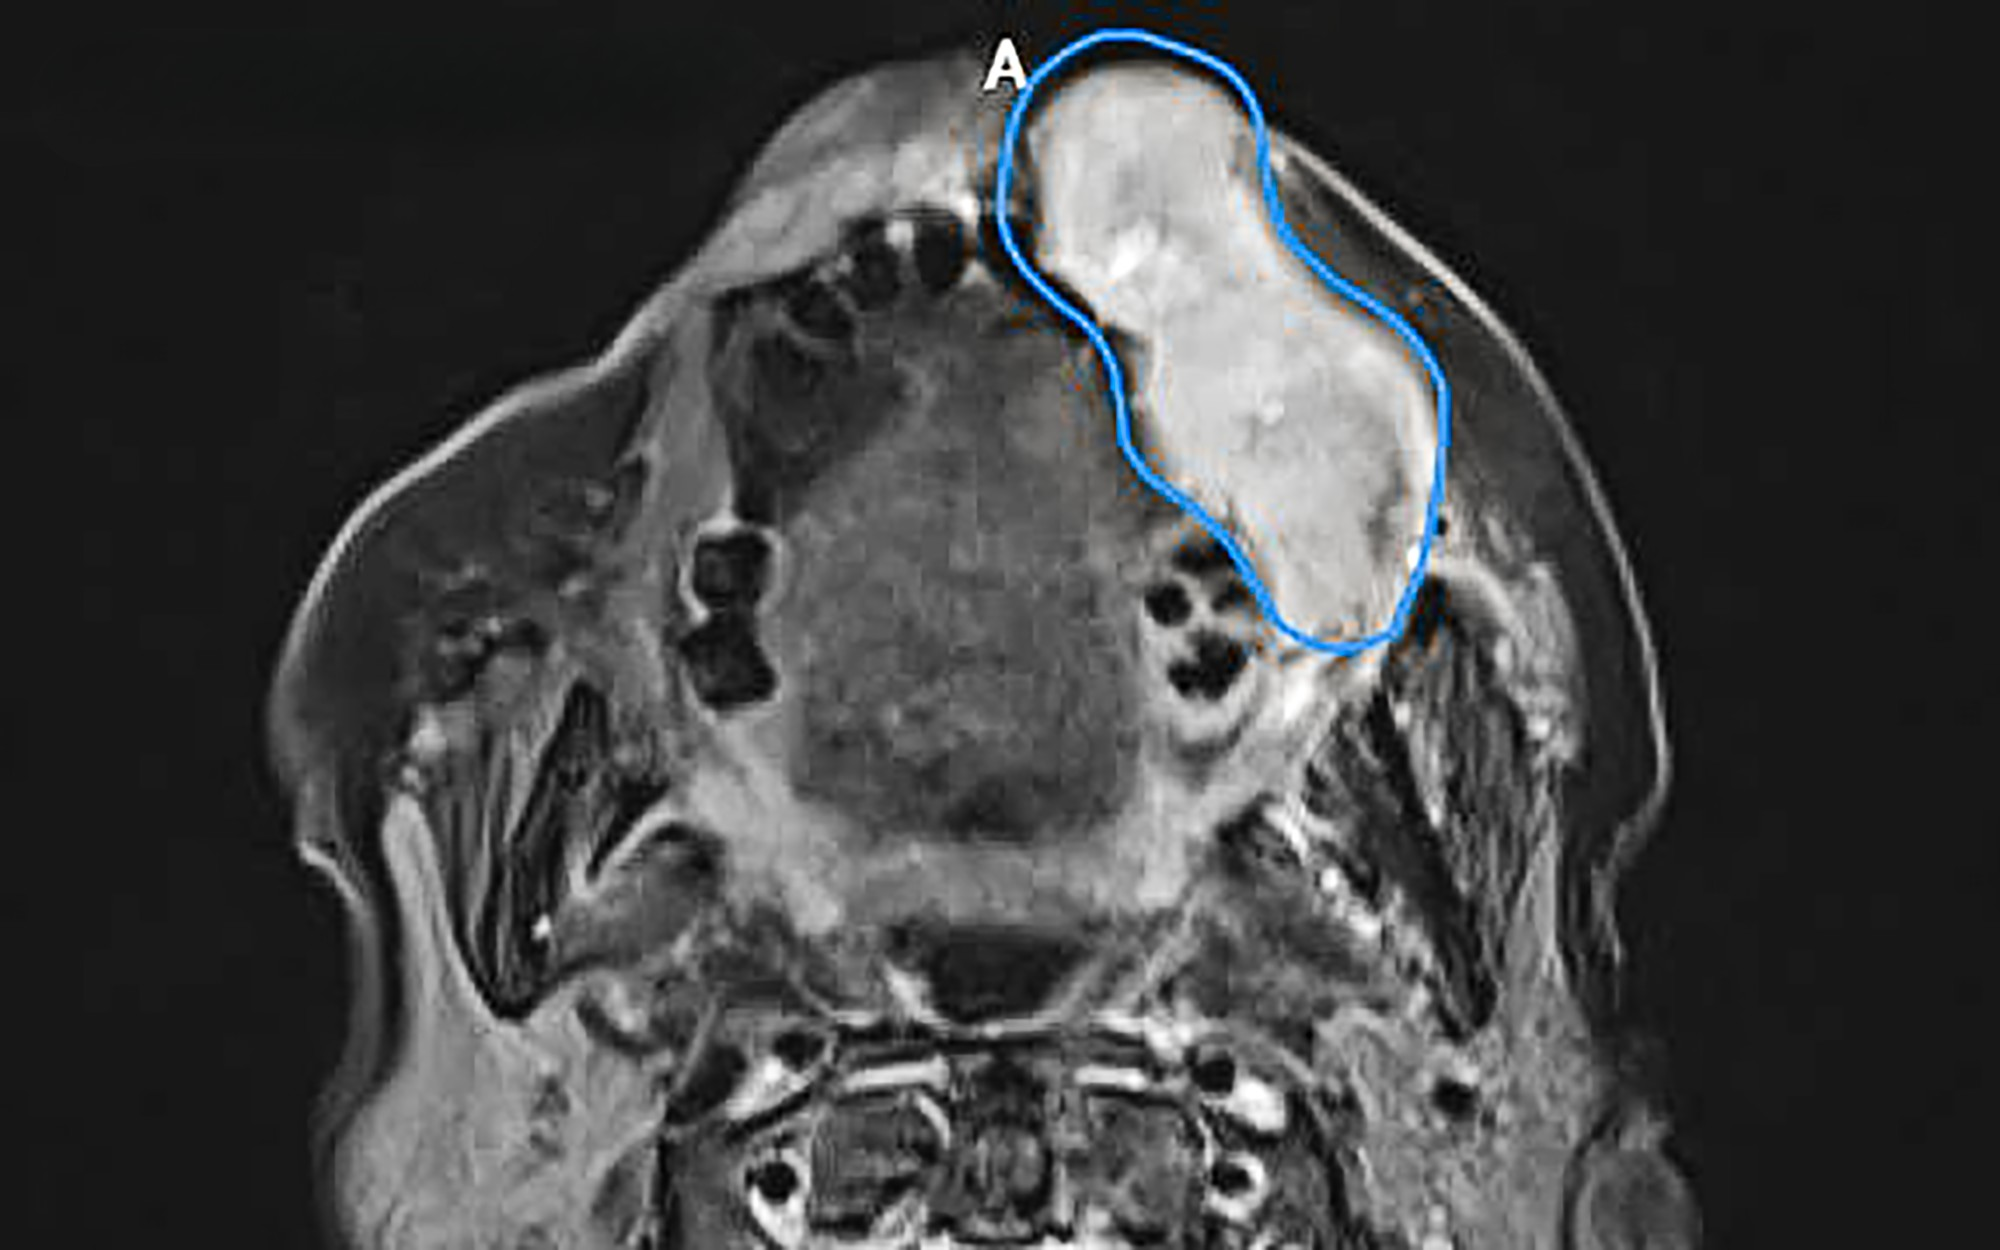

CT scan showing a malignant tumor (blue area) invading the cheek and lip from the oral mucosa. Photo: Tam Anh General Hospital

Mrs. Tinh, 80, developed a tumor six months ago. It progressively grew, causing her left face to swell, pushing out her cheek and lip, making them uneven and distorted. Inside her mouth, there were sores and discharge. The rapidly growing tumor caused pain, making it difficult for her to speak clearly and eat, leading to a 5 kg weight loss. A biopsy at Tam Anh General Hospital in TP HCM confirmed a 7 cm long, 4 cm thick stage three cheek lining cancer.

Doctors initially recommended surgical removal of the entire tumor, with wide margins and neck lymph node dissection to ensure all cancer cells were eradicated and to prevent metastasis and recurrence. To avoid a sunken cheek area post-surgery, which would impact chewing, speech, and aesthetics, reconstructive surgery using an autologous skin flap was planned. However, due to the patient's advanced age and multiple underlying health conditions, her family opted for radiation therapy instead of surgery.